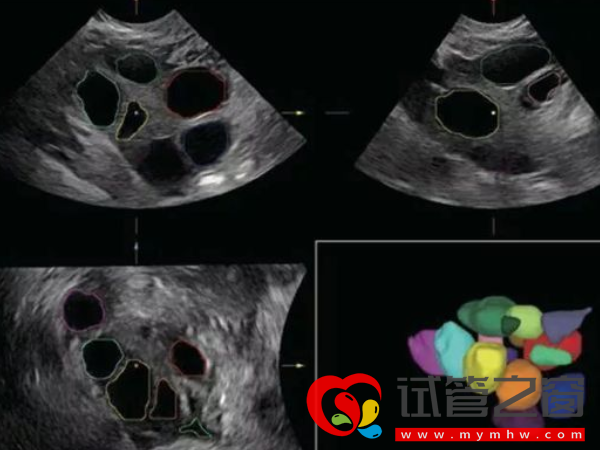

正常來講,空卵泡通過B超是無法準確的查出。B超監測卵泡的時候看到的是含有卵泡液的卵泡腔的大小,里面有沒有卵子是看不到的,因為卵子的體積很小,在超聲下根本看不到。只有在進去試管助孕是,取出卵子通過放大的顯微鏡才能知曉是不是空卵泡。通常所說到的三種檢查空泡的方式主要是:

- 1. B超:現在還沒有能夠100%確診為空卵泡的檢查方法,但通過B超動態監測能夠大致了解是否為空卵泡,但并不能確認是空卵泡。

1、借助B超動態監測就可以大致了解是否為空卵泡了,如果卵泡長到18-25cm,算是發育成熟,達到這個數值一般會排出。若監測期間卵泡并沒有按照這個趨勢發育,如明顯偏小,形狀很扁,這說明卵泡可能是空卵子;